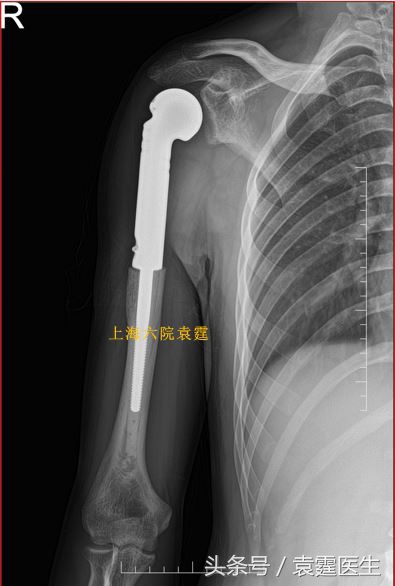

中度和高度恶性的,一般要把肿瘤涉及的部位全部切除,做关节置换,或者做肩关节融合术。关节置换有两种,一种是普通关节置换,这种关节置换后,由于肩袖组织被切除,肩关节功能大部分丧失,但这仍是目前应用最广泛的一种置换方法;第二是反式肩关节置换,由于肩关节的反式设计,即便肩袖组织被切除了,肩关节可以通过反式设计装置获得接近于正常的肩关节功能,其缺点,一是有严格的适应证,需要保留三角肌止点,这一条件绝大多数患者无法满足;二是费用太贵。

恶性肿瘤切除关节置换术后